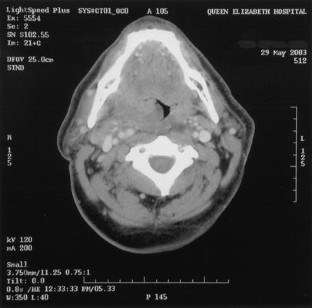

Fig. 1